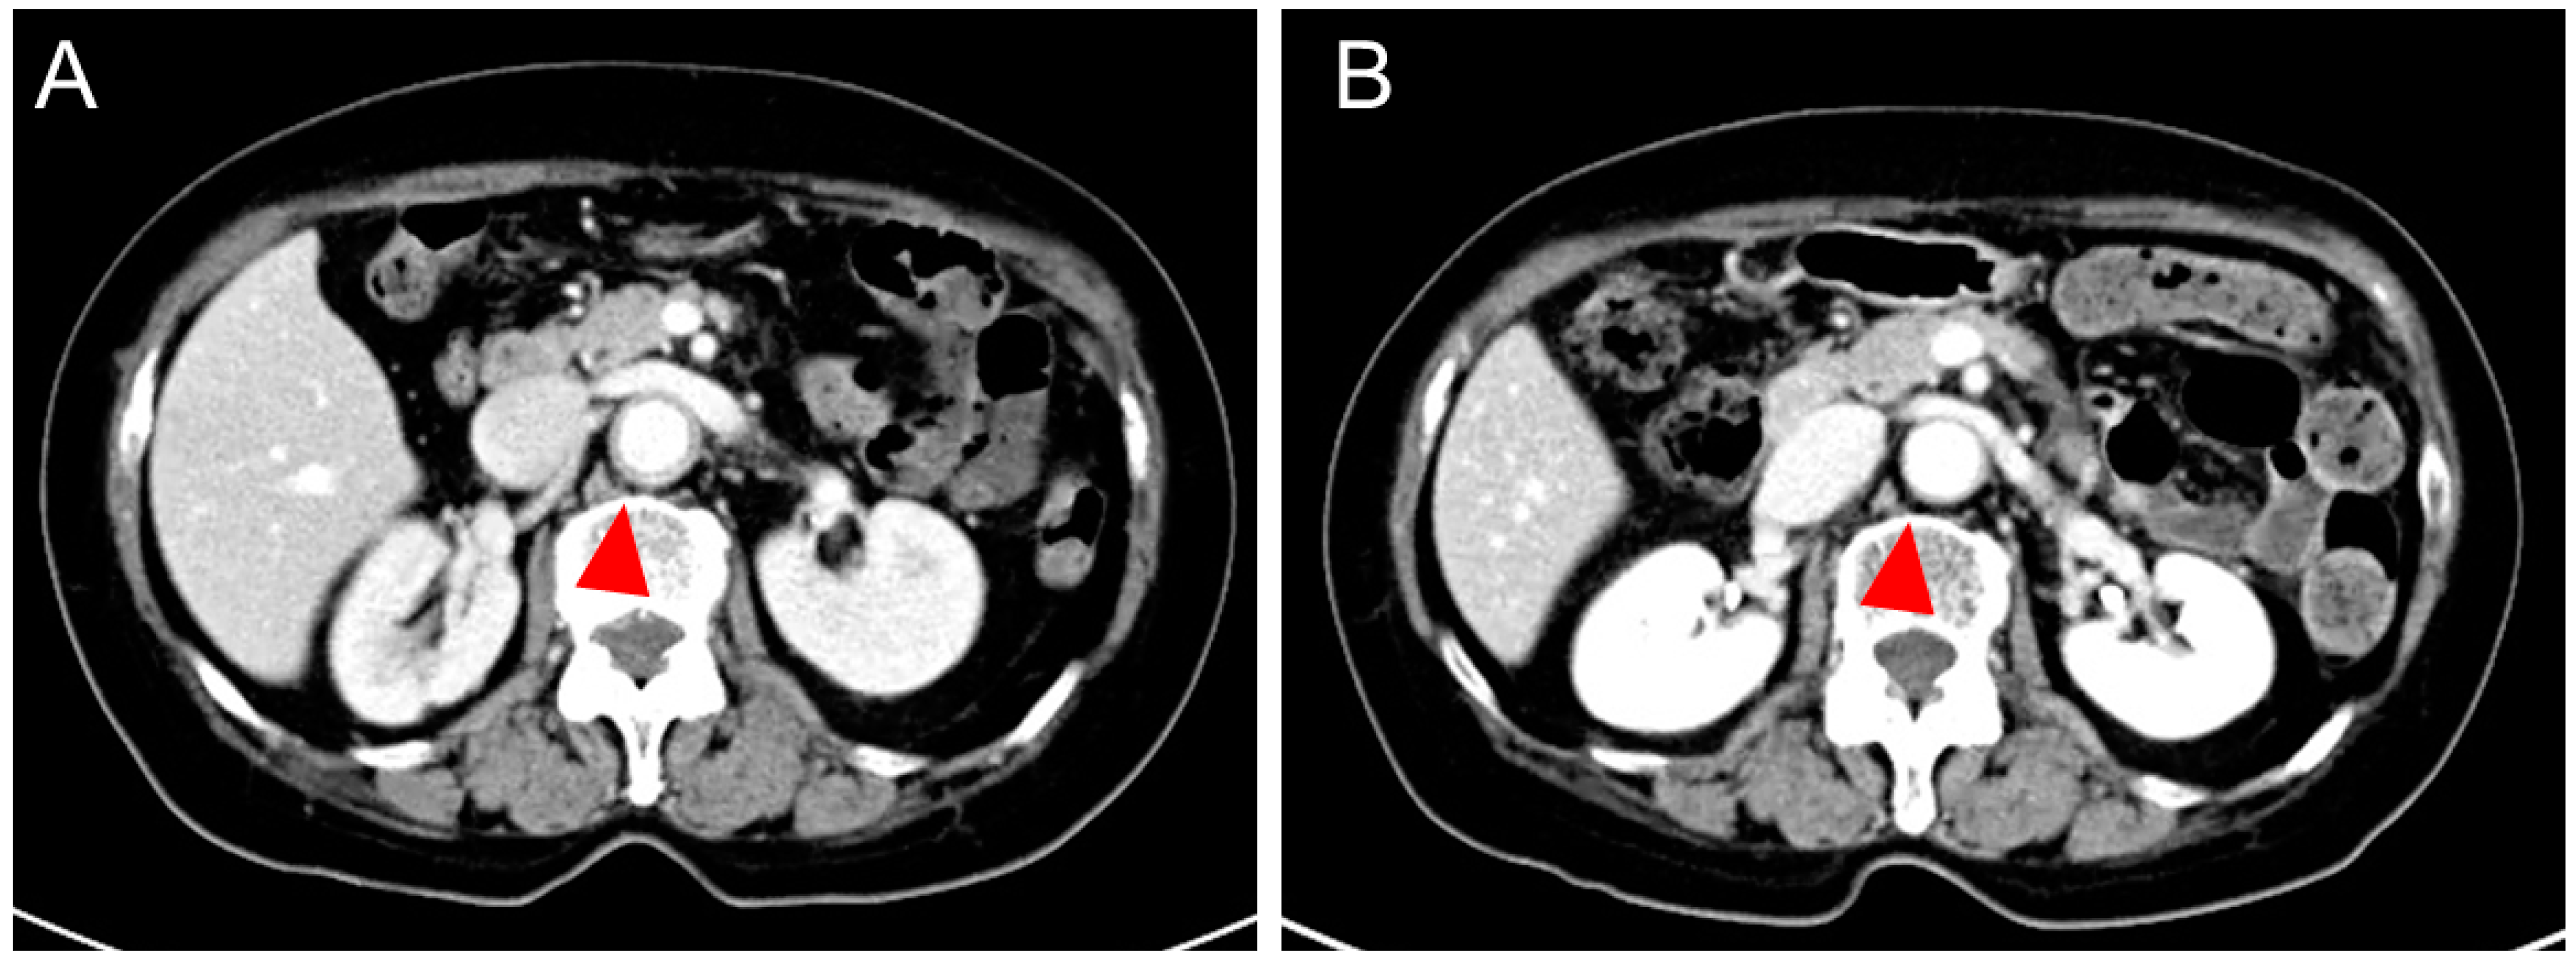

| Yoshimoto et al. (this case) | F, 69 | None | Headache, fever, abdominal pain, body weight loss | mRNA | 1 | 2 days | 38 days (5 weeks) | PET | GCA | LV-GCA | Ascending aorta, aortic arch, descending aorta, bilateral subclavian and iliac artery (PET) | 211 | 140 | 1g mPSL pulse PSL 50 mg TCZ 162 mg | 2 weeks | 2 years | Discharge (Remission with PSL 3 mg & TCZ) |